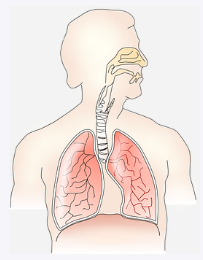

폐암은 한 마디로 폐에 생긴 악성 종양을 말하는데요. 폐 자체에서 암이 발병할 수도 있지만 다른 곳에 있던 암이 전이되어 폐에서 발전하는 경우도 있습니다.

폐암 초기증상 세 번째는 이상한 숨소리입니다. 숨을 쉬는데, 평소와 다른 소리가 나는 것 같다면 의심해 봐야합니다. 종양이 기도 근처에 자라고 있어서 숨소리가 이상하게 들릴 수가 있는 것이죠.

폐암 초기증상 네 번째는 가슴통증입니다. 종양이 폐의 벽 쪽에서 자라고 있다면 신경세포를 건드려서 가슴통증이 올 수 있습니다. 그리고 폐암은 갈비뼈 쪽으로 전이가 잘 된다고 하는데요. 그래서 그 주변에서 통증이 나타날 수 있습니다.